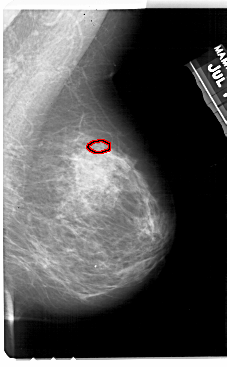

ics_version 1.0 filename A-1944-1 DATE_OF_STUDY 19 7 1994 PATIENT_AGE 72 FILM FILM_TYPE REGULAR DENSITY 3 DATE_DIGITIZED 8 7 1999 DIGITIZER HOWTEK 43.5 SEQUENCE LEFT_CC LINES 5431 PIXELS_PER_LINE 3106 BITS_PER_PIXEL 12 RESOLUTION 43.5 NON_OVERLAY LEFT_MLO LINES 5491 PIXELS_PER_LINE 3406 BITS_PER_PIXEL 12 RESOLUTION 43.5 NON_OVERLAY RIGHT_CC LINES 5116 PIXELS_PER_LINE 3046 BITS_PER_PIXEL 12 RESOLUTION 43.5 OVERLAY RIGHT_MLO LINES 5491 PIXELS_PER_LINE 3391 BITS_PER_PIXEL 12 RESOLUTION 43.5 OVERLAY |

FILE: A_1944_1.RIGHT_MLO.OVERLAY TOTAL_ABNORMALITIES 1 ABNORMALITY 1 LESION_TYPE CALCIFICATION TYPE PLEOMORPHIC DISTRIBUTION CLUSTERED ASSESSMENT 4 SUBTLETY 3 PATHOLOGY BENIGN TOTAL_OUTLINES 1 BOUNDARY |